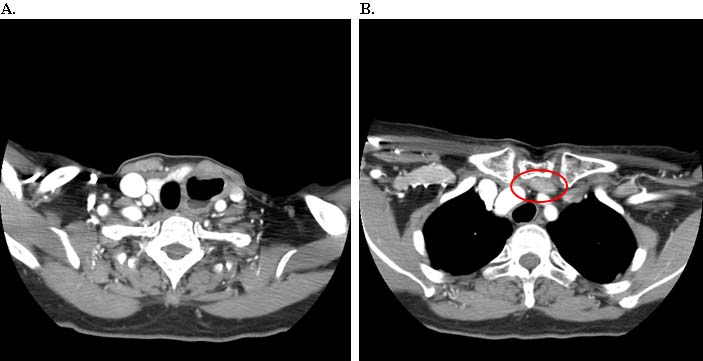

Intraoperatively, the gastric conduit was noted to be intimately compressed by the left SCJ (Figure 3A). The insertion of the sternocleidomastoid and other strap muscles were divided using electrocautery and the conduit was carefully bluntly dissected off the posterior sternum and left SCJ. The manubrial and clavicular segments of the SCJ were then resected, revealing the conduit underneath in good condition (Figure 3B). Care was taken to preserve the left internal mammary artery. Intraoperative EGD confirmed easy passage of the scope through the cervical anastomosis and into the gastric conduit with reduced extrinsic compression. Saline irrigation into the field and air insufflation of the conduit was used to confirm conduit integrity. A Savary-Gilliard guidewire was endoscopically passed and the anastomosis was carefully dilated using 42, 48, and 54 French (Fr) Savary-Gilliard bougie dilators (Cook Medical, Bloomington, IN) with minimal resistance. After removal of the guidewire, a 52 Fr Maloney dilator (Medovations, Milwaukee, WI) was also passed through the conduit without difficulty.